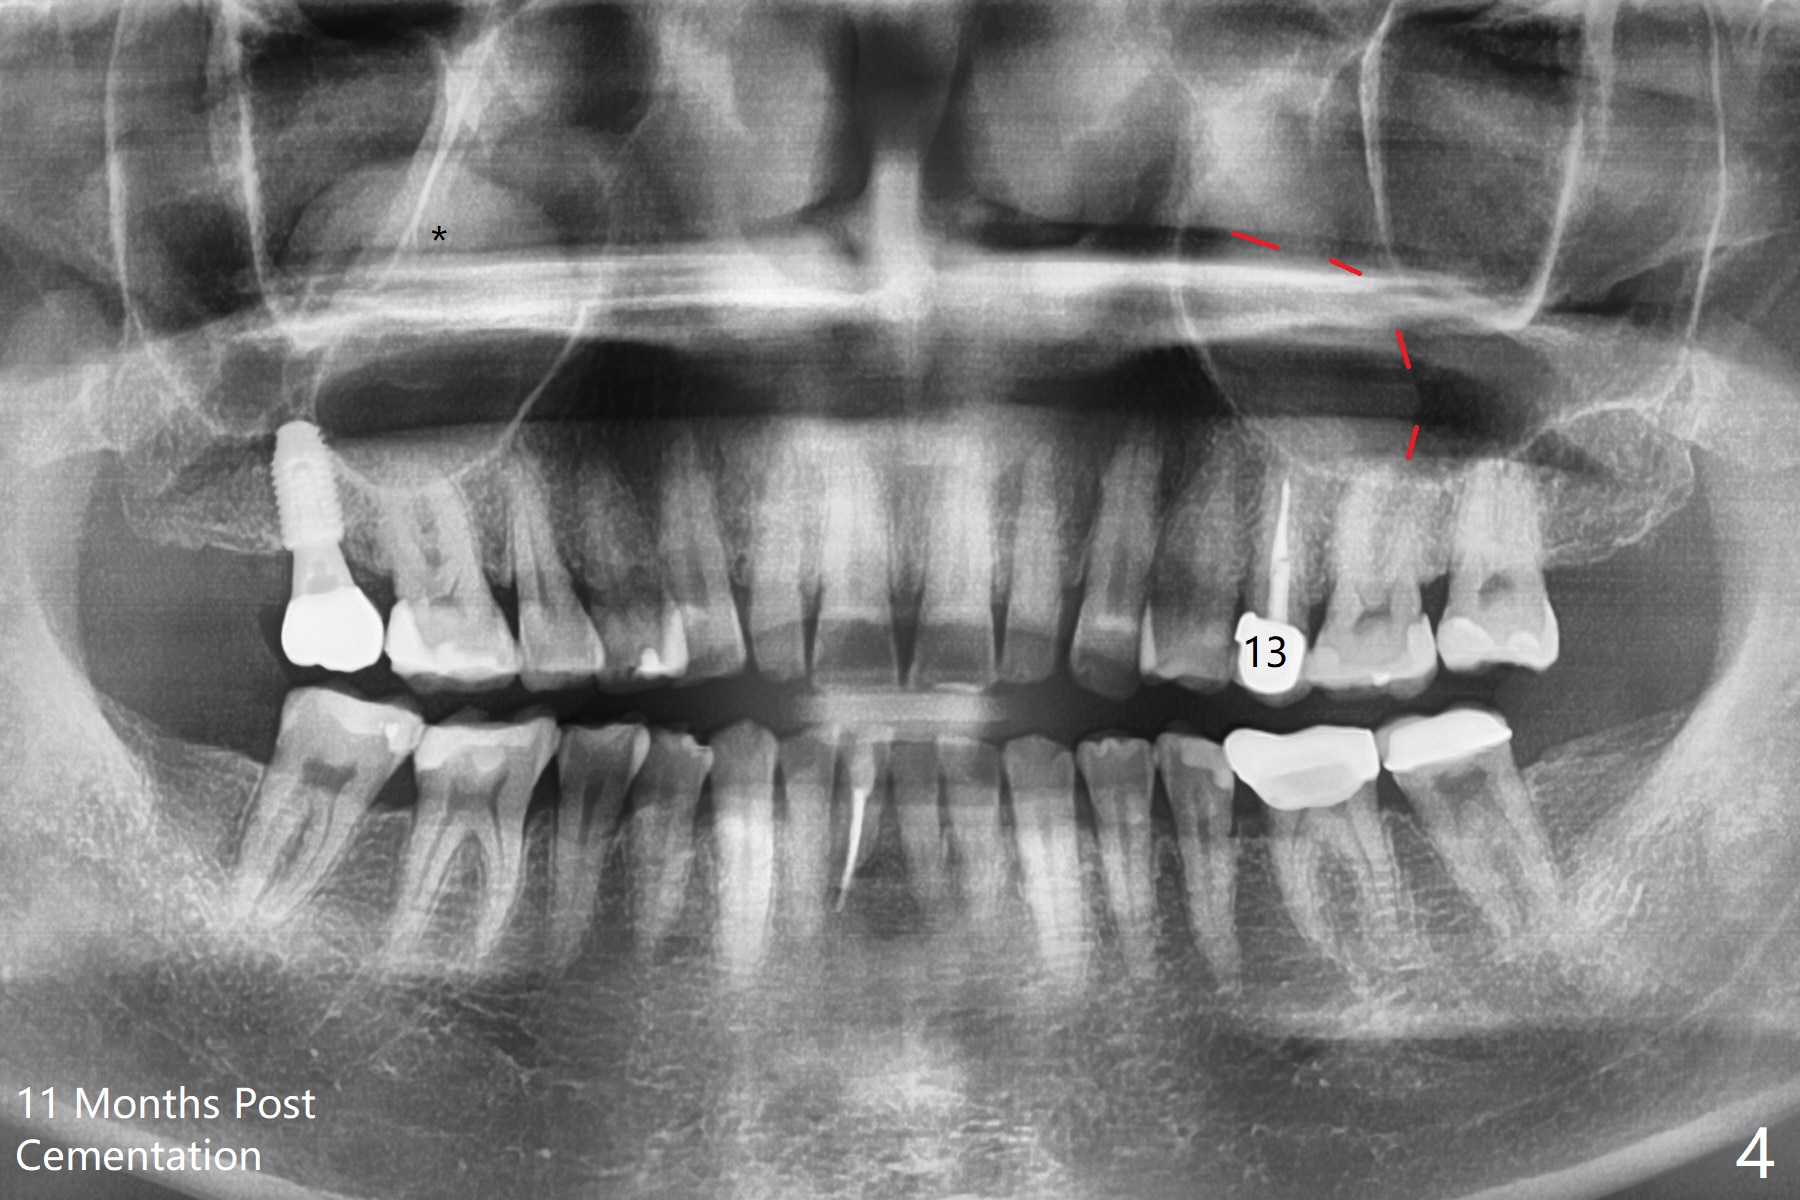

A 5x10 mm implant, placed in the buccal socket, achieves insertion torque of >55 Ncm after underprep (last drill 4 mm, as compared to 4.5 mm for normal prep). There is limited break of the sinus floor (Fig.1 arrowheads). No treatment is rendered for the mucocele. The implant heals without tenderness over the anterior sinus wall nearly 4 months postop (Fig.2). A crown is cemented 6 months postop (Fig.3 (5.2x4(4) mm abutment)); there is no gap between the abutment and implant, as compared to Fig.1,2 (6.5x4(3) mm). The implant functions without sign or symptom of bilateral sinusitis (no percussion associated with the tooth #13) 11 months post cementation (Fig.4). In fact the abutment is incompletely seated (Fig.5: <). Bone profile drill should be used to trim the mesial crest before reseating crown/abutment.